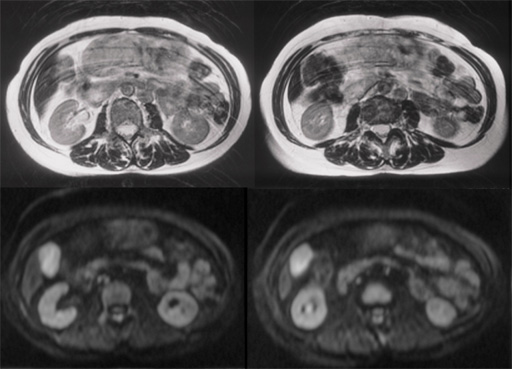

図1 図2 T2WI・DWI

図2 T2WI・DWI 図3